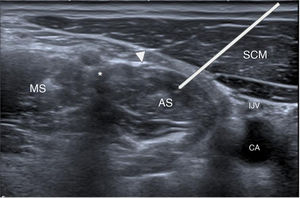

Ultrasound technique. The anterior scalene is identified deep to the sternocleidomastoid, with the carotid space—containing the major cervical vessels and the vagus nerve—located medially. Overlying the anterior scalene is the phrenic nerve, while the brachial plexus and subclavian vessels lie beneath it.23 (Fig. 5)

Figure 5.Anatomical plane for infiltration of the anterior scalene (AS), located deep to the sternocleidomastoid (SCM) and the phrenic nerve (arrowhead). The white line represents the theoretical course to be followed. The brachial plexus (asterisk) is visualised between the anterior and middle scalenes (MS), and medially the carotid space is identified, with the internal jugular vein (IJV) partially collapsed and the carotid artery (CA).

- 3

Infiltration. A 22 G needle is inserted from medial to lateral, passing through the sternocleidomastoid and avoiding the phrenic nerve to reach the anterior scalene.23